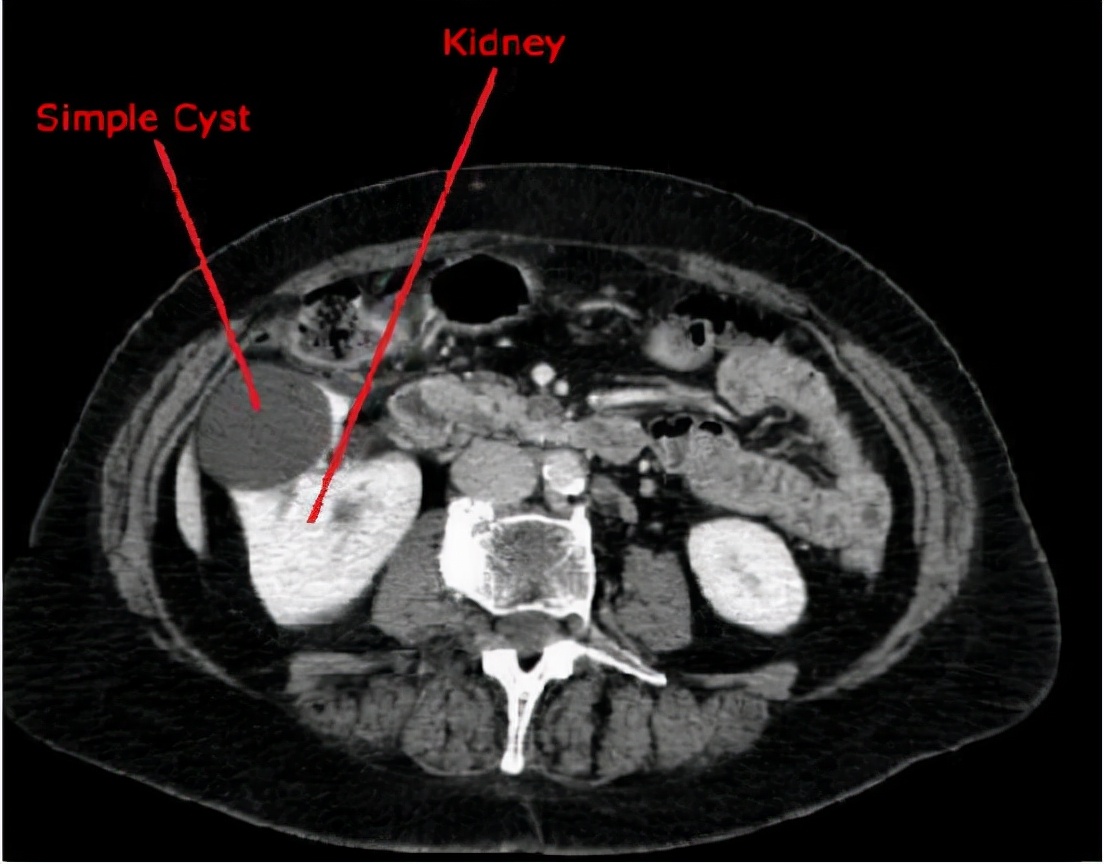

七、 单纯性肾囊肿

单纯性肾囊肿一般常见于中老年的男性,一般来说直径只要不超过2厘米那就不会引起人体的临床症状,也不会对身体的其他器官造成伤害,在日常生活中只需要每年定时的去进行尿常规、肾脏彩超、肾功能的检查就可以了。这种疾病一般是属于后天形成,也并不需要过多地进行特殊治疗。

单纯性肾囊肿的预防:就目前来讲是没有办法直接性的预防单纯性肾囊肿的。单纯性肾囊肿是人体肾脏之中存在单个或者是多个的小囊肿,一般多于体检之中发现。

单纯性肾囊肿若是较小,并且不会引起人体的任何症状,不需要过度的担忧,但若是已经产生了腰酸、腰胀以及其他临床症状,则需要及时的去泌尿外科进行手术,或者是其他治疗。